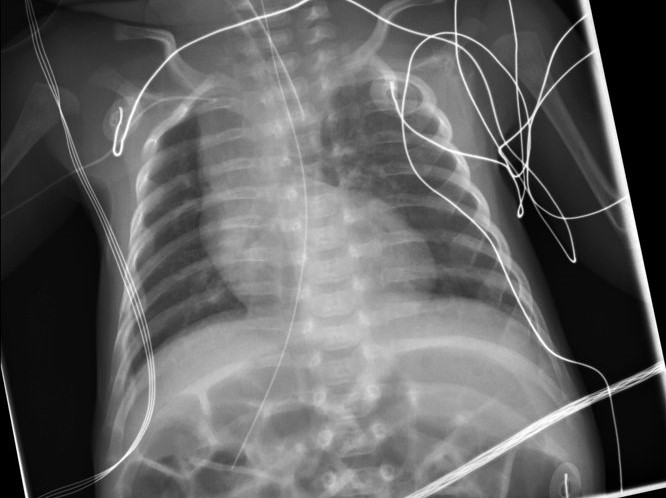

Ivemarkov syndróm (angl. Ivermark syndrome) je označenie pre veľmi vzácne a málo preskúmané geneticky podmienené vrodené ochorenia. Presná príčina jeho vzniku nie je známa, vyvolávajúci gén či gény neboli zatiaľ nájdené.  Syndróm sa prejavuje niekoľkými anatomickými odchýlkami. Postihnutému jedincovi chýba slezina, alebo má prítomných viacero malých  častí sleziny.

Ďalej sú prítomné abnormality kardiovaskulárneho aparátu a viacero vnútorných orgánov je u chorého na opačnej strane tela ako u normálnych ľudí. Toto obrátené usporiadanie orgánov sa odborne označuje ako situs viscerum inversus.Problémy chorým robia najmä vrodené srdcové chyby, ktoré môžu zhoršovať zásobenie tkanív tela kyslíkom a viesť k prejavom srdcového zlyhávania. Chýbanie sleziny má tiež svoje dôsledky, pretože slezina u detí je veľmi dôležitá pre správny vývoj imunitného systému. Choré deti preto trpia častými bakteriálnymi infekciami.